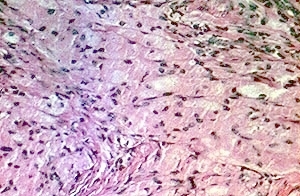

Graft versus Host Disease =داء رفض الطعم للمضيف Graft Versus Host Disease GVHD occurs in situations in which donor immunocompetent T cells transferred into allogenic hosts are incapable of rejecting them. The sources of the T cells include primarily peripheral blood stem cell and bone marrow transplants and, infrequently, unirradiated blood products , solid organ […]